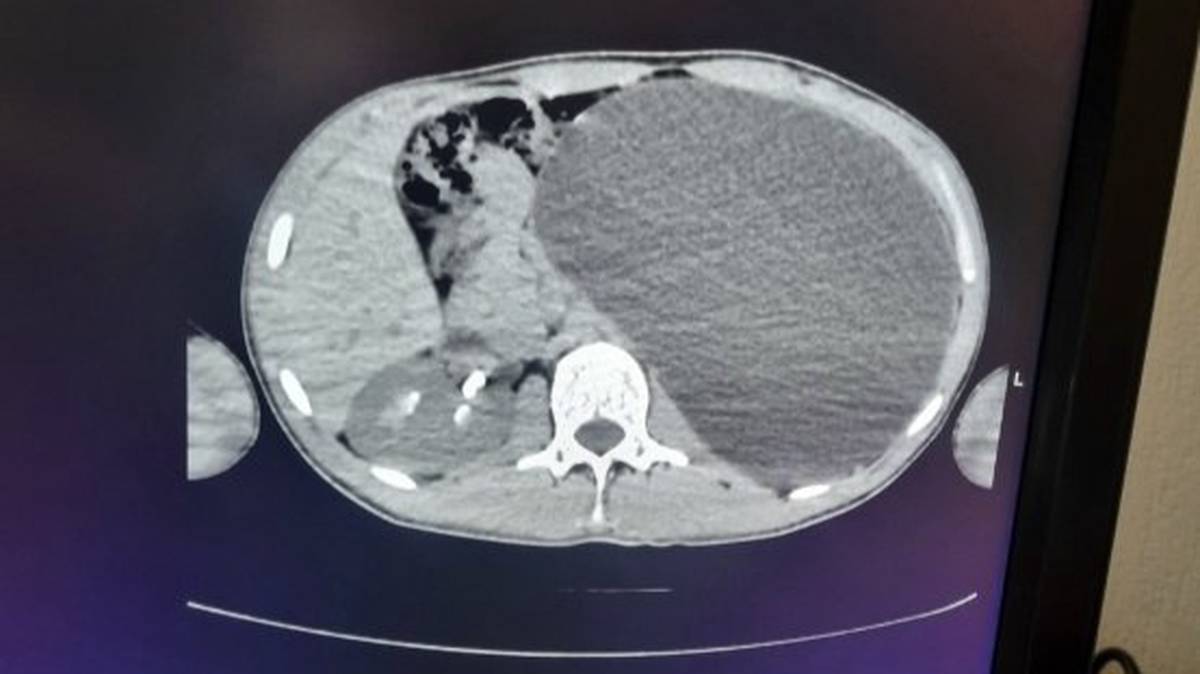

Новосибирские врачи удалили подростку почку размером с пятилитровую бутылку

Фото: Минздрав Новосибирской области / Telegram

Новосибирские врачи удалили 17-летнему юноше почку размером с пятилитровую бутылку, которая занимала почти весь объем живота. По словам медиков, такое отклонение было «бомбой замедленного действия». Об этом в среду, 18 февраля, сообщили в пресс-службе регионального Министерства здравоохранения.

— У нашего пациента почка достигла размеров пятилитровой бутылки! Она занимала почти весь объем живота и давила на все соседние органы. Это была настоящая «бомба замедленного действия»: любая травма, случайный удар в живот — и мешок мог разорваться внутри, — сказали в ДГКБ № 1.

В ведомстве рассказали, что хирурги откачали всю скопившуюся жидкость через четыре небольших прокола и удалили орган. Врачи уточнили, что пациент уже идет на поправку, сказано на сайте Минздрава.